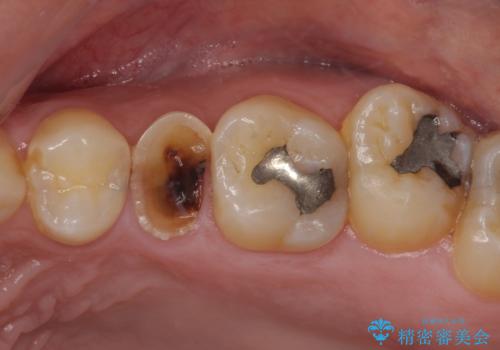

- 放置していたむし歯を治療したいとのことで来院された患者様です。

仕事が忙しいことを言い訳に虫歯を放置してきたものの、強い痛みを感じたことがあったため、重い腰を上げて来院されたとのことでした。

強い痛みのあった歯は、既に神経組織が失活しており根管治療が必要でした。

反対側の歯は、歯根だけが歯肉に埋もれて残っている状態のため、抜歯が必要な状態でした。

歯根だけとなっている歯はインプラントに、神経組織の失活している歯は根管治療を行い、いずれもオールセラミッククラウンにて補綴治療を行うこととしました。